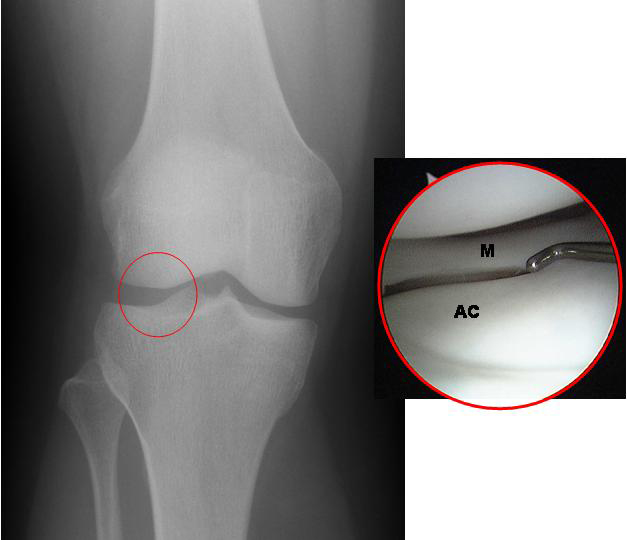

- Imaging tests: While X-rays may not always detect hairline fractures initially, they can be useful in ruling out other injuries. MRI or bone scans are often more effective in identifying stress fractures.

Can hairline fractures be seen on regular X-rays? Not always. Hairline fractures may not be visible on X-rays for several weeks after the injury occurs. This is why additional imaging techniques are often necessary for accurate diagnosis.

- MRI: The best imaging test for determining hairline fractures is an MRI. This test uses magnets and radio waves to provide images of your bones. An MRI will determine a fracture before an X-ray can.

It’ll do a better job of determining the type of fracture as well. - X-ray: Hairline fractures often aren’t visible on X-rays immediately after the injury. The fracture may become visible a few weeks after the injury takes place, when a callus has formed around the healing area.